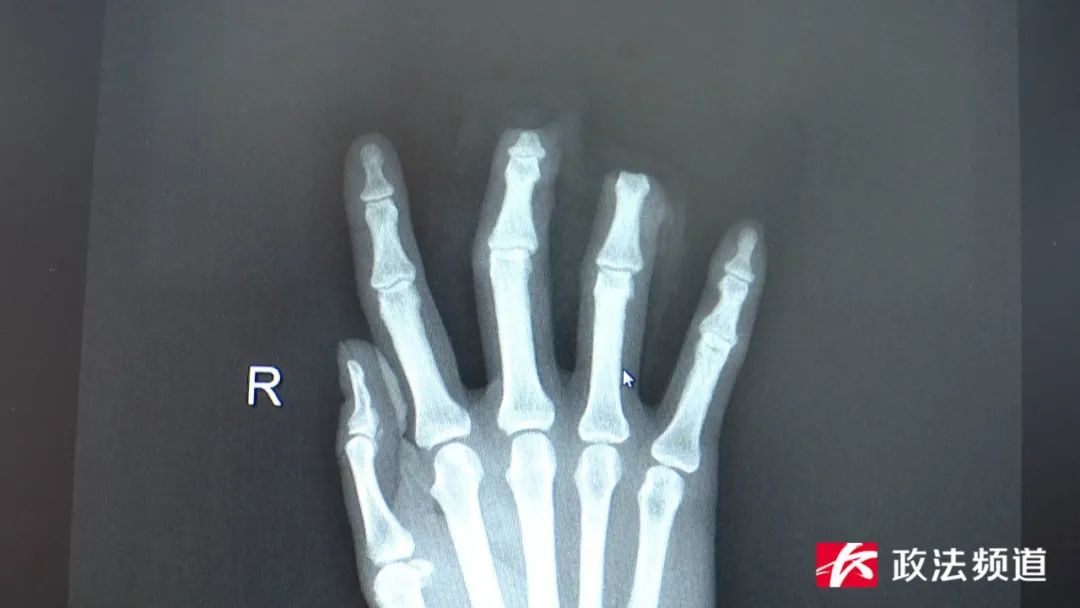

醫(yī)生介紹,李女士受傷的手指為末節(jié)離斷,此處的血管就和樹枝的末梢一樣十分細(xì)小,且離斷指體斷面有挫傷,因此術(shù)中會(huì)有一定的困難。入院后,醫(yī)護(hù)人員立即進(jìn)行相關(guān)檢查檢驗(yàn),并與麻醉手術(shù)科溝通協(xié)作,以最快速度完善了術(shù)前準(zhǔn)備,為李女士在全麻下進(jìn)行右中環(huán)指末節(jié)斷指再植術(shù),重建了斷指的血運(yùn),手術(shù)順利,目前李女士的斷指成功存活。

“手部的功能可能需要一定的恢復(fù)時(shí)間,但基本的功能應(yīng)該不會(huì)受到太大影響!焙鲜〉诙嗣襻t(yī)院手足外科主治醫(yī)師徐昱提醒,無論是工作還是日常生活,大家一定要對刀具進(jìn)行妥善保管,使用時(shí)也要謹(jǐn)慎當(dāng)心。一旦發(fā)生意外,首先要做的就是止血,然后及時(shí)就醫(yī)治療。手足外科主任李奇?zhèn)ブ魅吾t(yī)師介紹,患指(肢)的熱缺血時(shí)間是決定成功再植的一個(gè)重要因素。肢體離斷時(shí),斷指的血液循環(huán)中斷,在斷指殘留的血液、氧氣、營養(yǎng)物質(zhì)可短暫維持組織存活。當(dāng)殘指在常溫下放置2-4小時(shí),開始進(jìn)行無氧代謝。當(dāng)無氧持續(xù)6-8小時(shí),肌肉組織逐漸變性并釋放出鉀離子、肌紅蛋自和肽類等有毒物質(zhì),這些有毒物質(zhì)會(huì)造成細(xì)胞膜損害、細(xì)胞變性、壞死。因此,斷指再植具有限時(shí)性,一般認(rèn)為夏季手指離斷6-8小時(shí)內(nèi),冬季為10-12小時(shí)內(nèi)為最佳時(shí)段,但是超過時(shí)間也不要放棄,用干燥冷藏法或用無菌敷料、清潔布類包好帶去醫(yī)院。